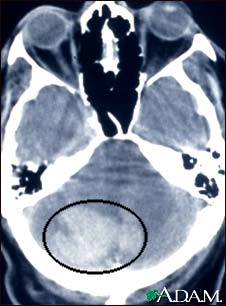

Intracerebellar hemorrhage - CT scan

Intracerebellar hemorrhage shown by CT scan. This hemorrhage followed use of t-PA.